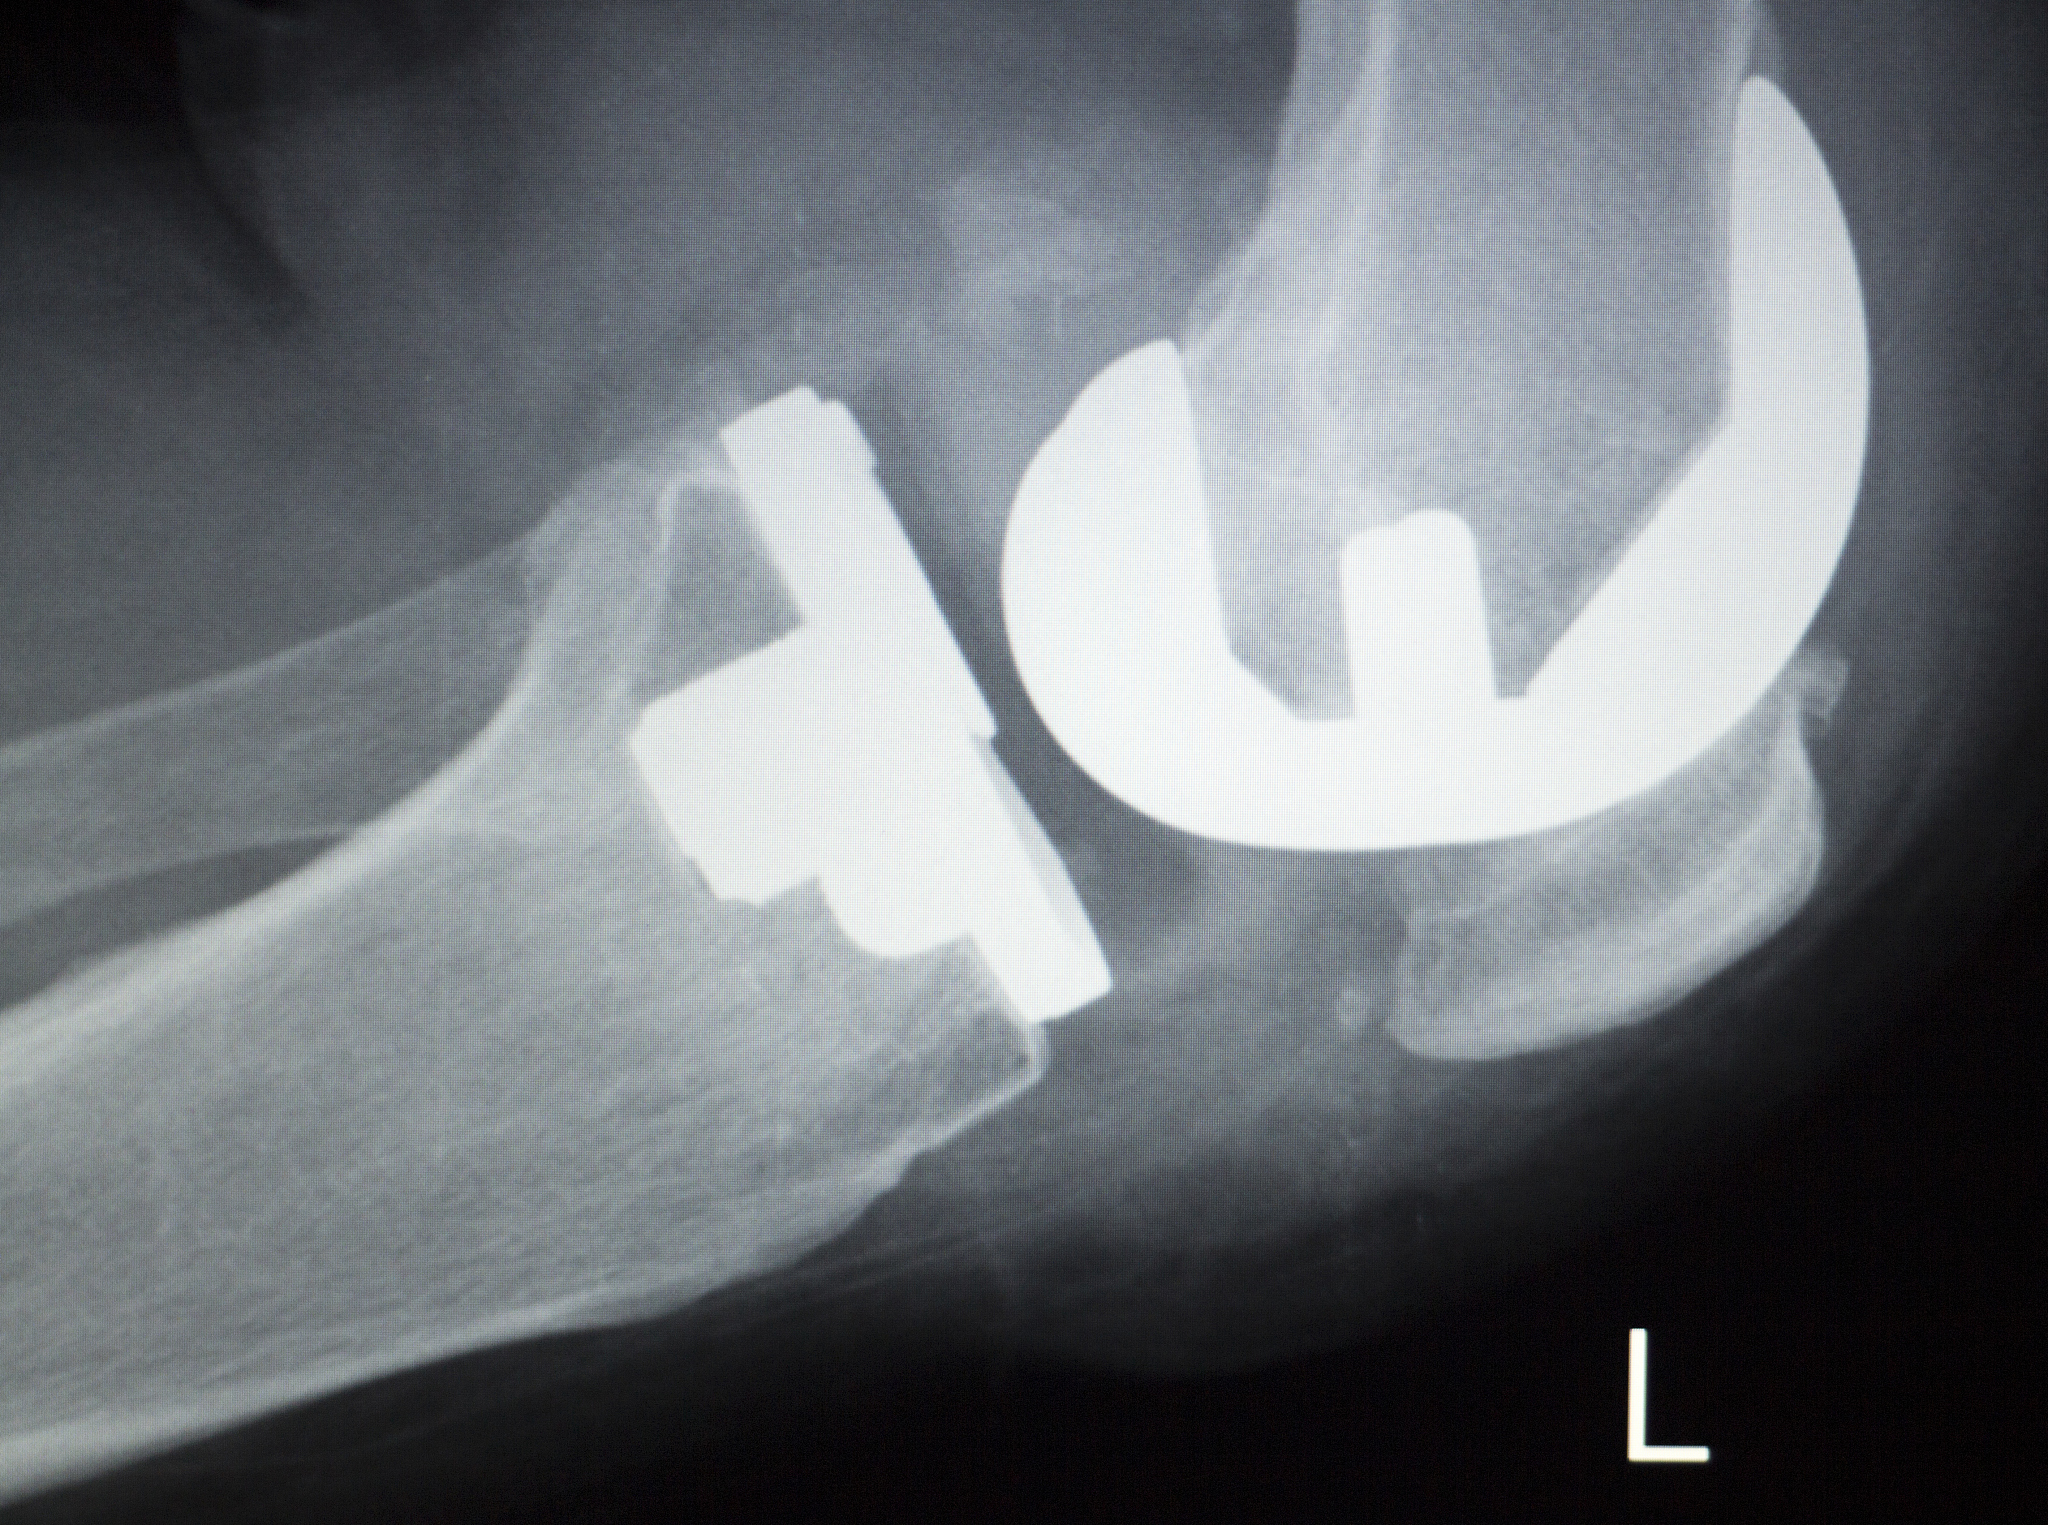

3. 诊断

通常通过病史询问、体格检查和影像学检查(如X光、CT或MRI)进行诊断。